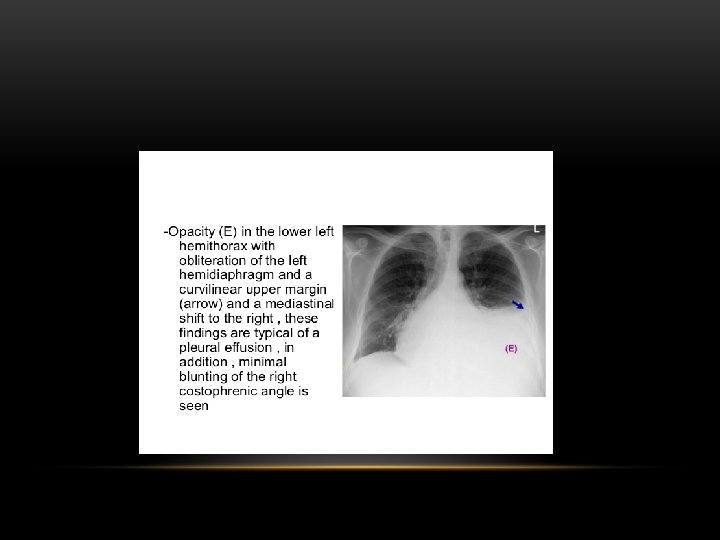

Pleural Effusion Fluid accumulates in the pleural space. Irrespective of the nature of fluid, radiologically they will look similar. Radiological criteria are: Density In dependent portion (Costophrenic angle in PA view). Blunting of costophrenic angle Lack of identifiable diaphragm (silhouette sign principle).

Causes of pleural effusion: -Infection -Subphrenic abscess. -Malignant neoplasm -Cardiac failure -Pulmonary infarction -Collagen vascular disease -Nephrotic syndrom Modalities for pl. effusion diagnosis: -Plain chest x ray. -Ultrasound -Computed tomography

Pleural Effusion • Homogenous density • Loss of cardiophrenic angle • Loss of diaphragmatic and right cardiac silhouette